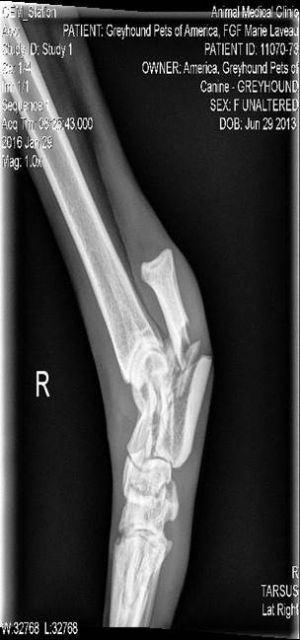

Bishop just arrived from the Palm Beach Race Track. He is a gorgeous, 73lb black male with ears that stand straight up when he is curious about something. He raced only 14 races before injuring his leg in a fall on July 1st. His leg was fixed, splinted and rehabbed by a vet in Florida that worked with his racing owner and trainer. He is out of the splint now and healed up so was cleared to travel to our group to be adopted. He turned 2 on October 15th. His sire is Venus Espinosa and his dam is Kiowa Lee Philli. Bishop is a friendly, playful boy with a very cool personality. Bishop loves to go for rides in the car and is a very good traveler. He loves to run around and play with toys and his old leg injury doesn't seem to slow him down. He plays nicely with the other dogs in his foster home and is all about getting his people and his friends to play with him. Although he is silly and playful he does calm down. He is a very sweet, snuggly boy that is quiet in his kennel. He is going to be a fun boy for a lucky family. He did pass his cat test with no interest so should be fine to live with cats and small dogs. He will need to be discouraged from rough play with either though because of the size difference. He didn't even get excited when he saw rats at PetSmart so appears to be able to live with small animals. |